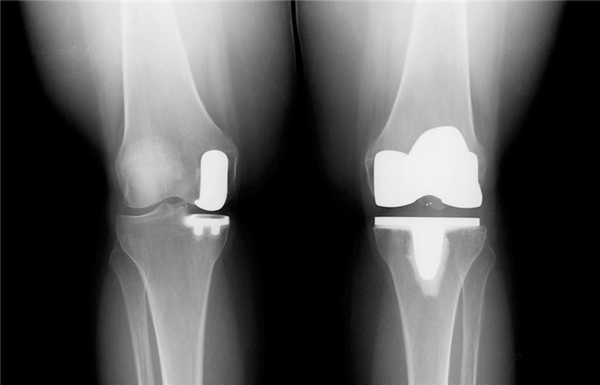

Замена коленного сустава (ЗКС) - метод хирургического лечения последствий дегенеративно-дистрофического патогенеза колена. Цель операции полное восстановление функций проблемного отдела конечности за счет замены необратимо пораженного сочленения эндопротезом. Гонартроз 3-й степени (в 85% случаев) самая частая причина.

Артроз коленного сустава на рентгене.

Посмотрите на рентген, на нем вы видите, до какой степени при запущенном гонартрозе изношен гиалиновый хрящ, обеспечивающий гладкое скольжение суставных поверхностей. Концевые участки костей грубо деформируются нарушая функции сгибания и разгибания конечности вызывая интенсивный болевой синдром.

Две техники операции у одного пациента.

Одномыщелковая замена сустава на рентгене.

Сравнение двух типов операций.